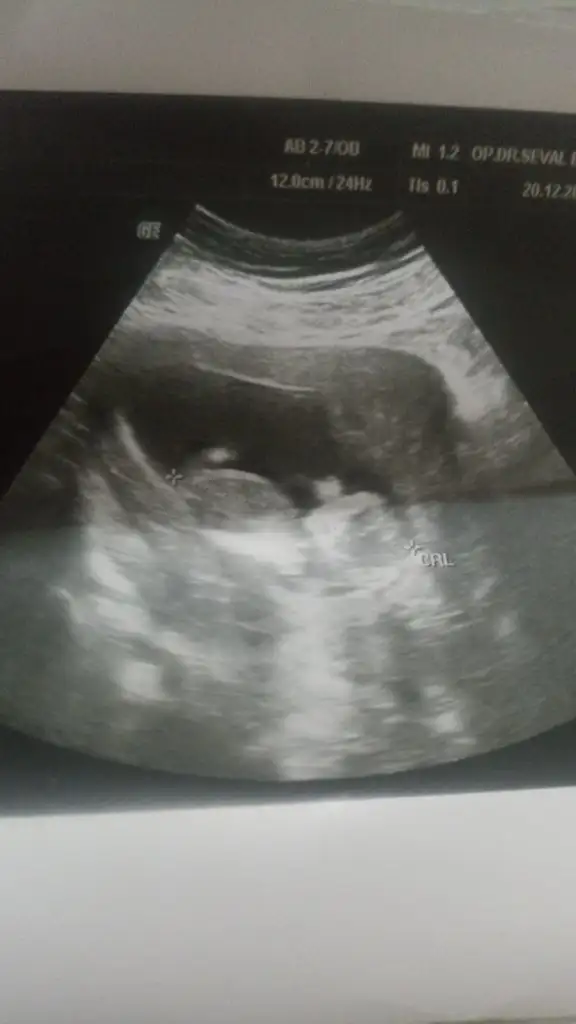

Merhaba sadece bunu verdi doktor bebeğim 11+6 haftalıkMerhaba sağlıkla kucağınıza alın inşallahbaşka foto yok mu ben pek anlayamadım burdan . Bir de kaç haftalık bebeğiniz? K kivi06pamuk

Yaaa yiğenim 11+3 de kız dediler şuan 1 buçuk yaşında o yüzden meraklandımO haftalar çok erken doktor bana 12. haftada %80 kız dedi 15. Haftada erkek olduğu kesinleşti

O bacağı diye tahmin ediyorum çıkıntı yok gibi sanki ama belli olmaz tabiErkek gibi nuba göre

Ama nub bende tutmamıştı, kız diyolardı oğlum oldu yani kız

Kıza benziyorMerhabaaa bizede yorum yapar mısınız 12 haftalığız